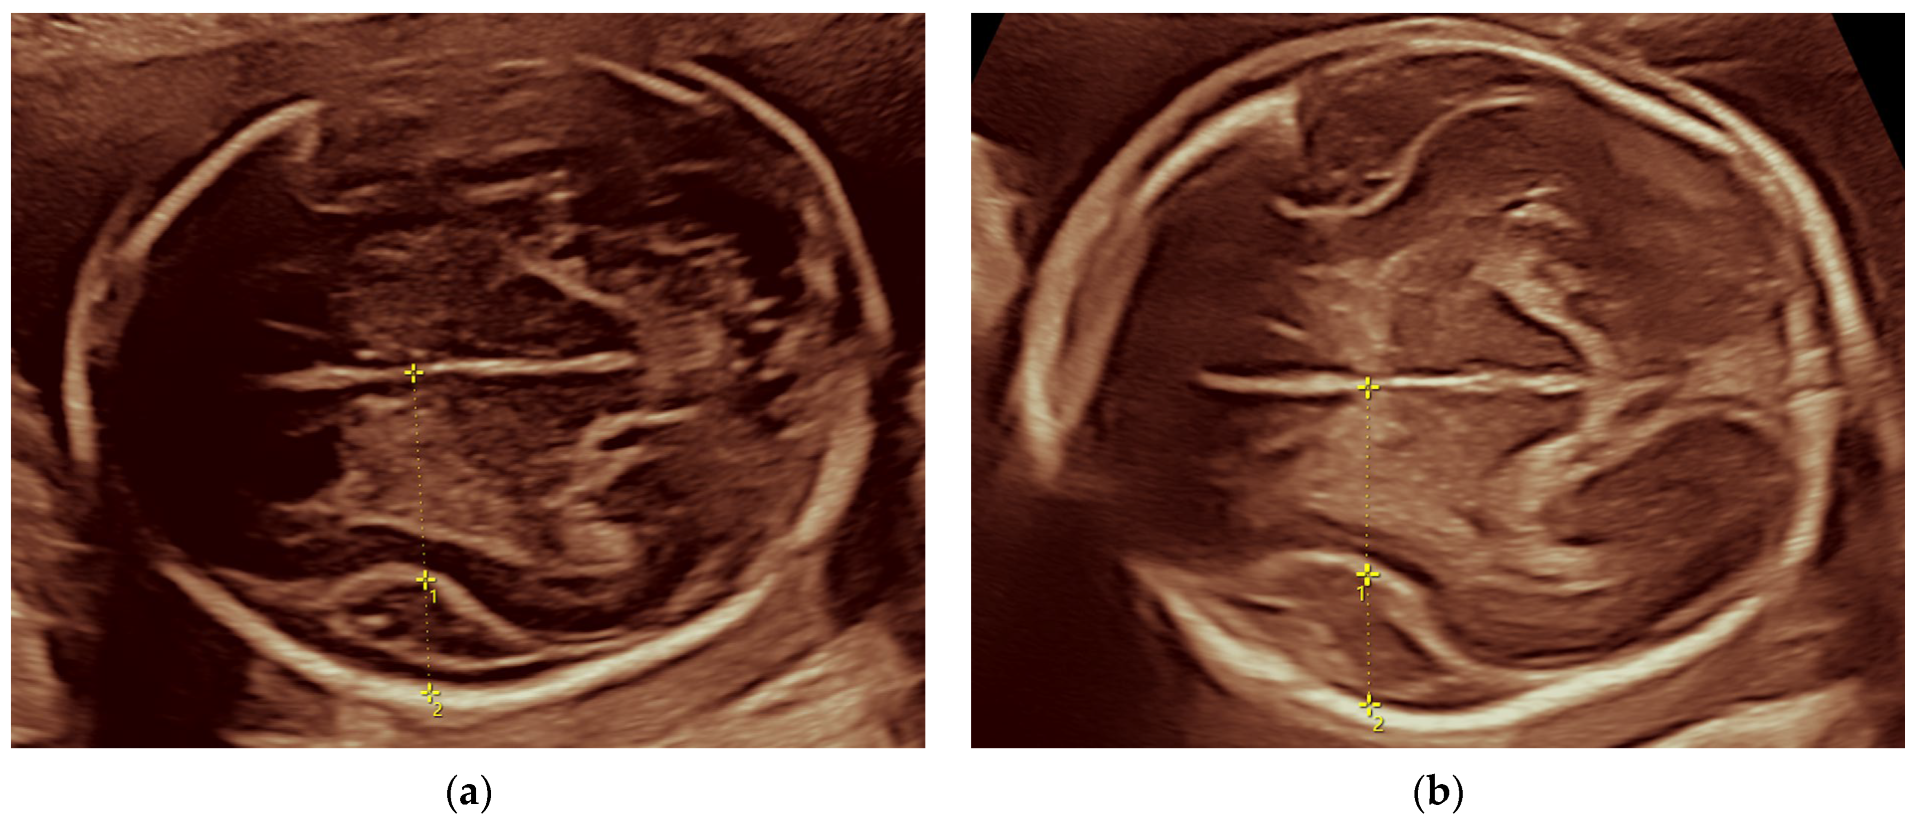

2.1.2. Ultrasound Findings

2.2.2. Ultrasound Findings